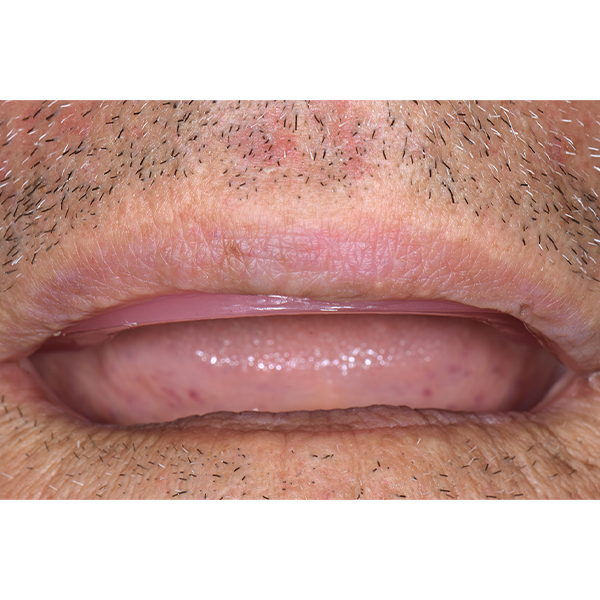

Après la mise en moufle et l'ébouillantage, les dents ont été repositionnées, conditionnées et des caractérisations blanchâtres, pourpres, orange clair, bleues et roses ont d'abord été réalisées au niveau du le bouclier labial. La base a ensuite été incrustée de résines pour prothèses de couleurs orange-rouge, rouge foncé, rouge clair, rose et rose foncé, et tous les polymères à chaud ont été pressés en une seule fois. Après le stockage sous pression, les prothèses finies ont été démouflées, finies et polies. La stratification anatomique tridimensionnelle de VITAPAN EXCELL en masse d'émail, de collet et de dentine avait un aspect absolument naturel dans l'anatomie muco-gingivale reproduite de la base prothétique. Le patient a pu s'habituer rapidement à sa nouvelle prothèse, notamment grâce à l'effet esthétique réussi. Après une courte phase d'adaptation et des corrections minimes dans l'environnement biodynamique, il s'est très bien débrouillé avec sa première restauration prothétique amovible complète et en était pleinement satisfait.